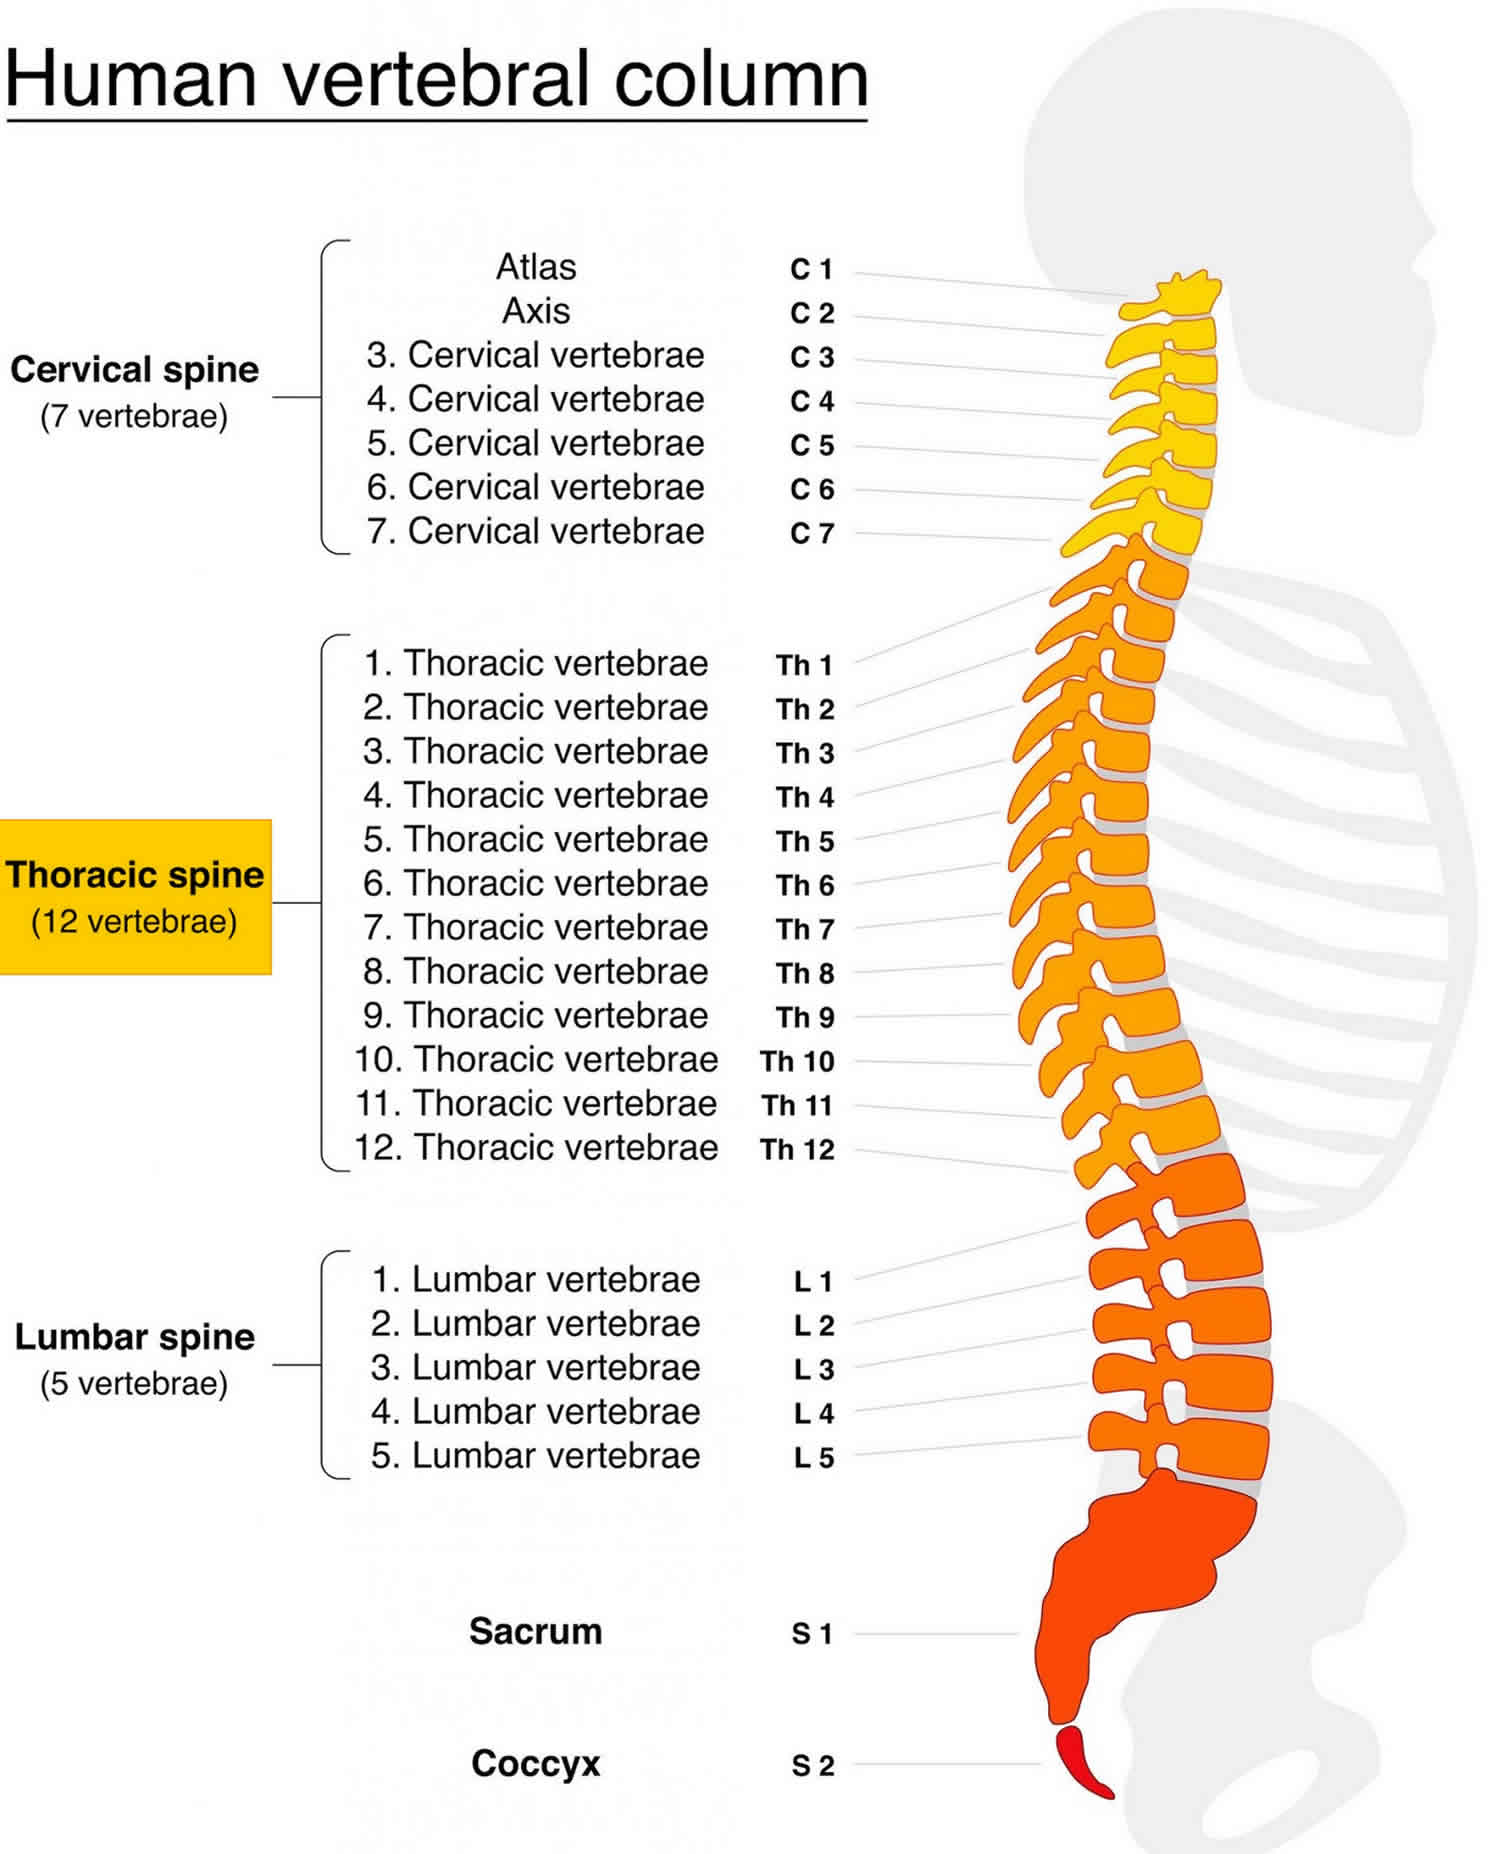

The number of intervertebral discs in the human spine class 11 biology CBSE

Anatomy of the Spine | Globus Medical

Information about spine and intervetebral disc anatomy – Dr David Oehme …

Anatomy of the Spine | Wessex Spinal Surgeon

Spine Anatomy and Back Pain – The Core Expert

human spine anatomy diagram

Diagram Human Spine Name Description All Sections Vertebrae Vector …